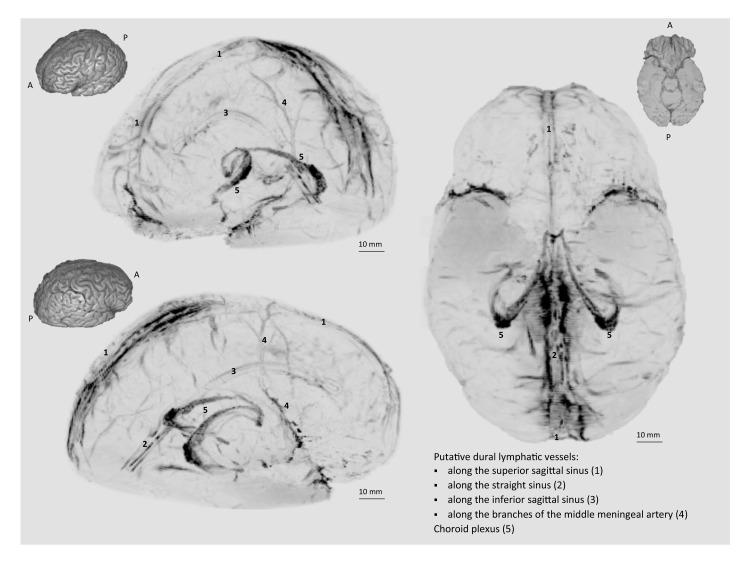

Here, we report the existence of meningeal lymphatic vessels in human and nonhuman primates (common marmoset monkeys) and the feasibility of noninvasively imaging and mapping them in vivo with high-resolution, clinical MRI. On T2-FLAIR and T1-weighted black-blood imaging, lymphatic vessels enhance with gadobutrol, a gadolinium-based contrast agent with high propensity to extravasate across a permeable capillary endothelial barrier, but not with gadofosveset, a blood-pool contrast agent. The topography of these vessels, running alongside dural venous sinuses, recapitulates the meningeal lymphatic system of rodents. In primates, meningeal lymphatics display a typical panel of lymphatic endothelial markers by immunohistochemistry. This discovery holds promise for better understanding the normal physiology of lymphatic drainage from the central nervous system and potential aberrations in neurological diseases.

在这里,我们报告了脑膜淋巴管在人类和非人类灵长类动物(普通狨猴)中的存在,以及使用高分辨率临床 MRI 对其进行非侵入性成像和体内绘图的可行性。在 T2-FLAIR 和 T1 加权黑血成像中,淋巴管增强与钆布醇增强,这是一种具有高倾向穿过可渗透的毛细血管内皮屏障外渗的基于钆的造影剂,但与血池造影剂钆氟塞特不同。这些与硬脑膜静脉窦并行运行的血管的拓扑结构再现了啮齿动物的脑膜淋巴系统。在灵长类动物中,脑膜淋巴管通过免疫组织化学显示出典型的一组淋巴管内皮标志物。这一发现有望更好地理解从中枢神经系统进行淋巴引流的正常生理学以及神经疾病中的潜在异常。